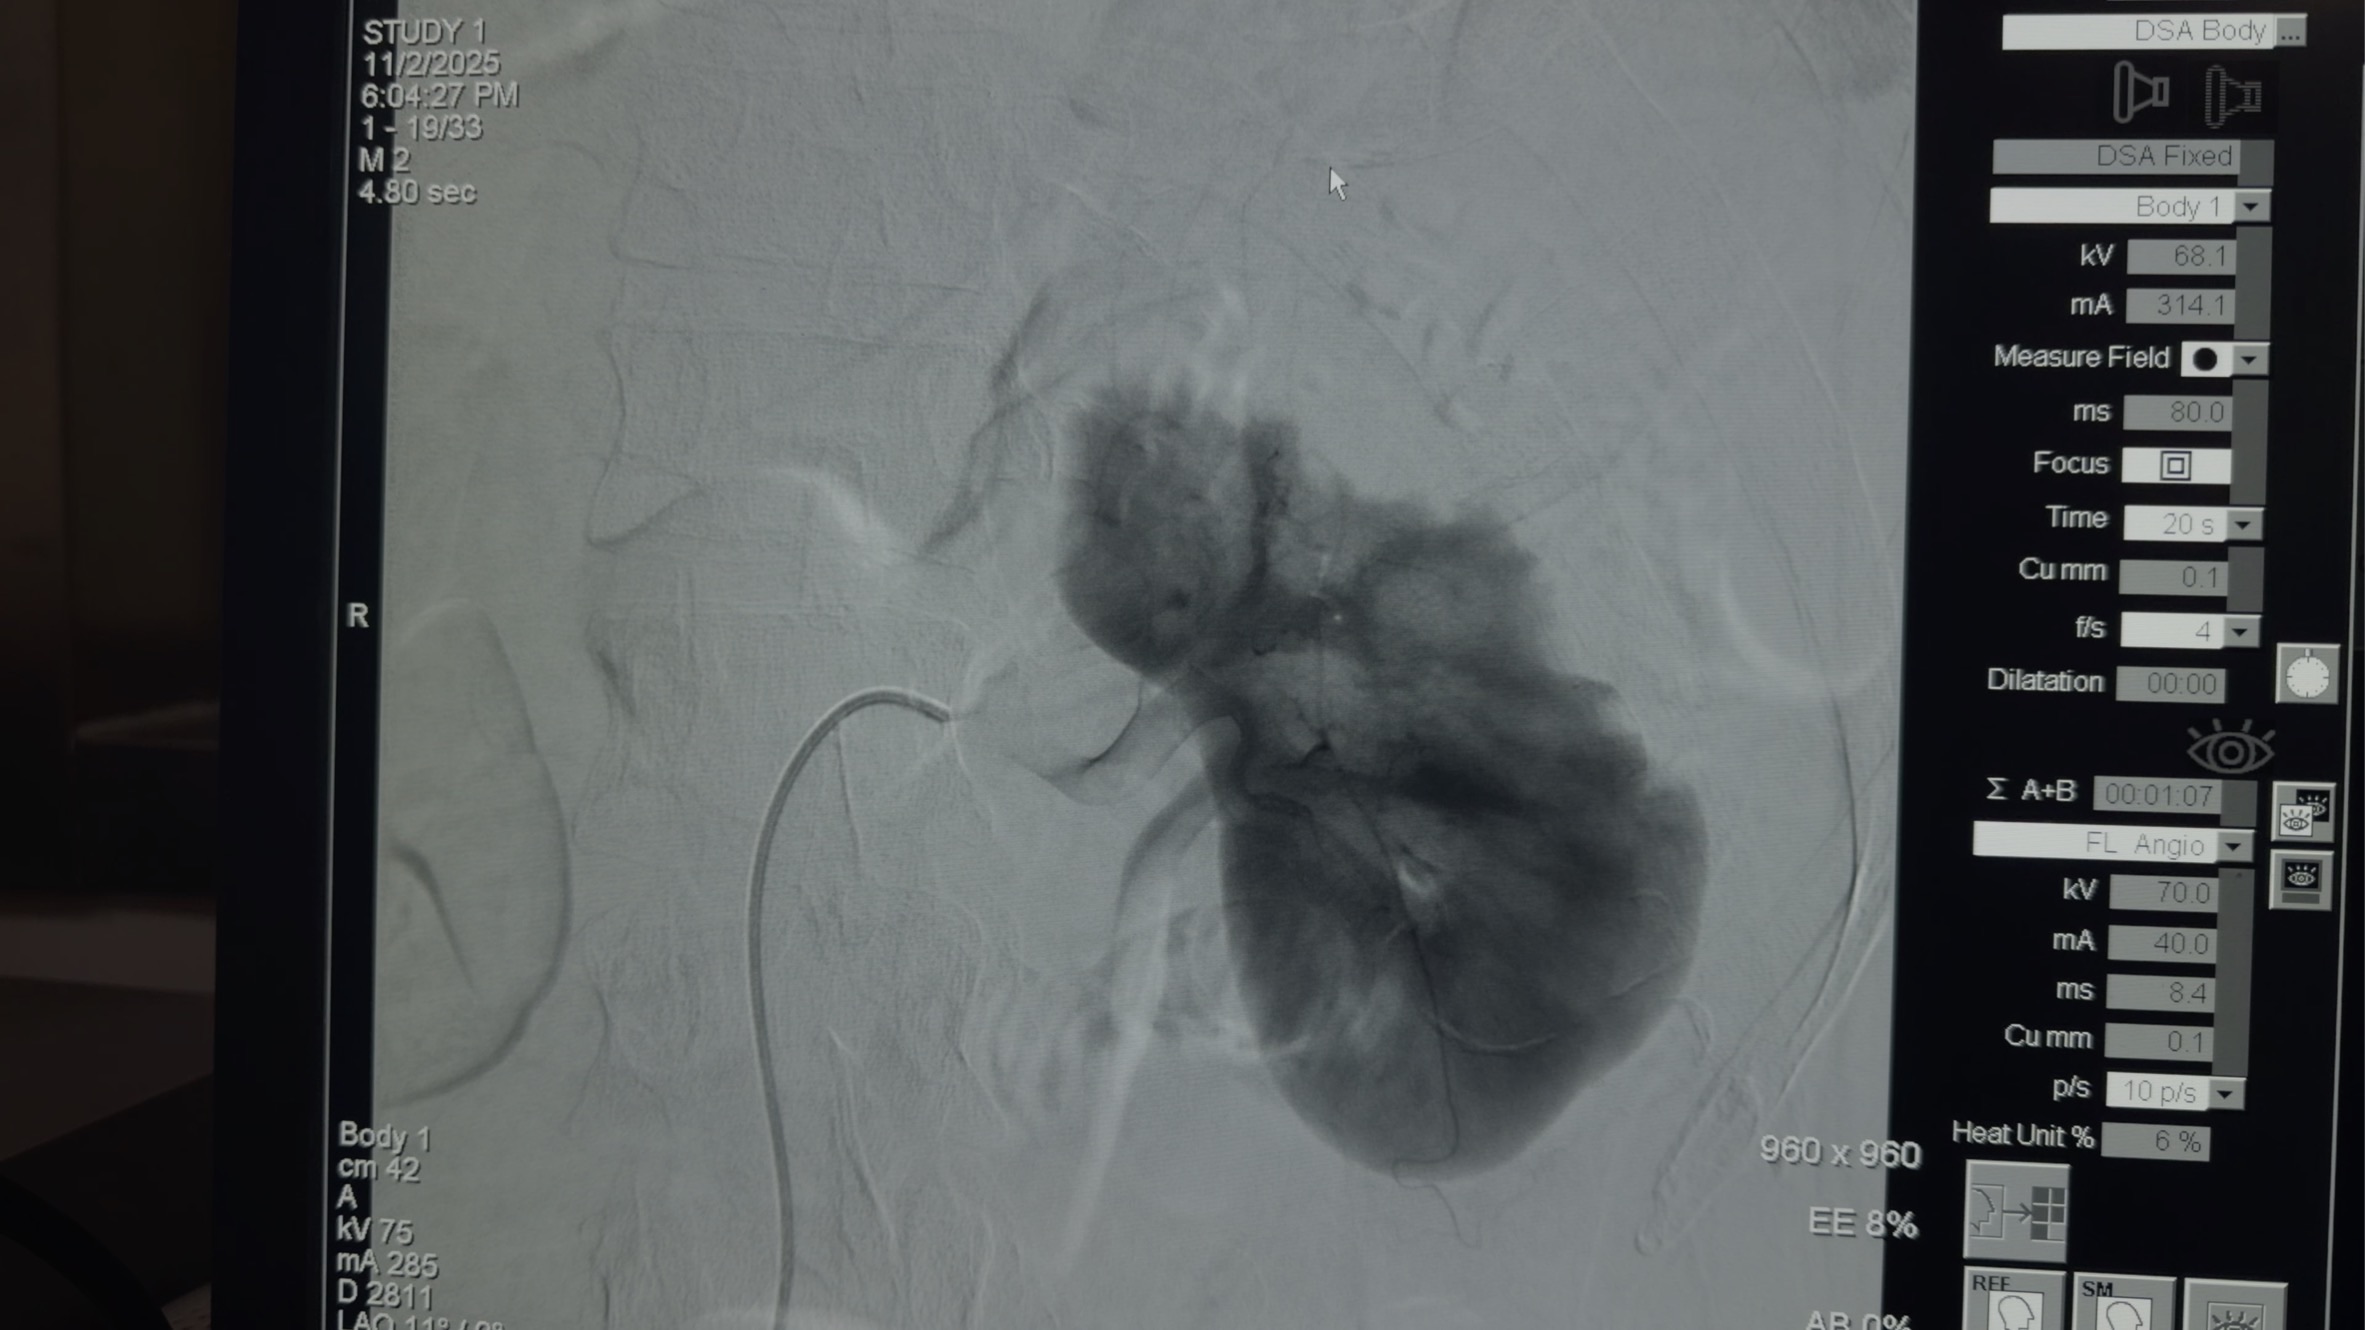

入院3小时后,患者进行经股动脉穿刺肾动脉造影、置管溶栓治疗。

置管后予以尿激酶40万单位,一日两次溶栓。予以积极补液扩容、抑酸保护胃粘膜、抗感染、改善微循环等治疗。